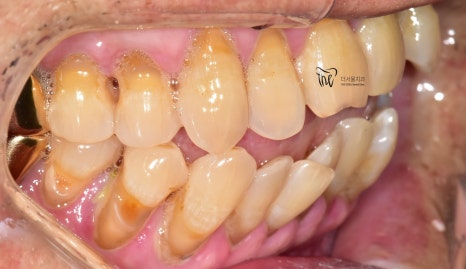

나아가, 측면에서 찍은 사진들을 보면

앞서 설명드린 내용들이 그대로 드러나죠.

어금니들쪽을 보면, 잇몸과 가까운 치경부쪽에

다 파절증의 증세를 보여주고 있으며

이미 임플란트 시술 또는 크라운 보철이

다 수복이 되어 있습니다.

이 말은, 이미 과거 상당히 마모 현상이

진행이 되었을테고 이에 따라서 이 시림 현상이나

통증을 느끼셨기 때문에 보철 치료로

대체를 하신 것으로 소견됩니다.